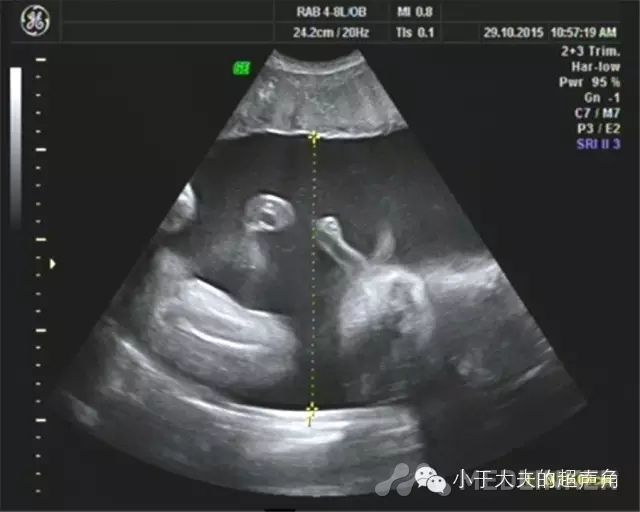

超声表现宫内见两胎儿,其间可见羊膜分隔。A胎儿位于右侧腹,双顶径82mm,头围298mm,腹围338mm,股骨长64mm,体重约2693mm±393g。 胎位:臀位。羊水:最大深度约151mm。CDFI:S/D:4.36,RI:0.77脐带:胎儿颈部未见U型血流。 胎心率:135次/分。大脑中动脉CDFI:S/D:1.78,RI:0.44胎儿腹围明显大于孕周,相当于37W+5天,腹腔内显示液性暗区回声,最宽处约9mm,胎儿心脏扩大,胎儿全身皮下组织增厚,头颅及躯干周围被无回声或低回声区包绕,呈“外套” 样水肿。B胎儿位于左侧腹,双顶径81mm,头 281mm,腹围282mm,股骨长63mm,体重约1914± 279g。胎位:头位。羊水:因右侧腹胎儿挤压,羊水显示不清。CDFI:S/D:3.18,RI:0.69脐带:胎儿颈部未见U型血流。 胎心率:161次/分。两胎儿胎盘:位于前壁,厚约39mm,成熟度:I级。

超声诊断双胎。A胎儿:臀位,孕相当于34周+1胎儿声像图异常改变,心胸比增大,腹腔积液,胎儿皮下水肿,S/D比值增高。(不除双胎输血综合征可能,建议产前咨询及进一步检查)B胎儿:头位,孕相当于32周,胎心偏快4行剖宫产术剖宫产术后确诊为:双胎输血综合征,胎盘中间有很多血管交通支,如下图:图5、双胎输血综合征,可见胎盘中间部分有很多血管相互交织成的血管网 TTTS需鉴别的疾病1、羊水过少&羊水过多:两个羊膜腔内羊水量存在差异并不少见,单凭羊水量差异不足以诊断TTTS。一个胎儿严重的羊水过少或过多,而另一个胎儿羊水正常,应高度怀疑双胎之一孤立性的胎儿异常或胎儿生长受限所致。2、不相称胎儿生长:不相称胎儿生长仅仅是一个征象,简单的是指两胎儿生长明显不同,或不相称胎儿发育异常。TTTS的特征为两个胎儿都经历着病理过程,因此两个胎儿都有异常的超声表现。

双胎输血综合征(TTTs)是指两个胎儿循环之间通过胎盘的血管吻合进行血液输注,导致双胎均出现明显的血流动力学异常,从而引起的一系列病理生理学改变及临床表现。1TTTSの特点①单个胎盘;②两胎儿间伴有纤细分隔隔膜;③两胎儿性别相同;④受血儿羊膜腔内羊水过多,最大羊水池深度>8cm;供血儿羊膜腔内羊水过少,最大羊水池深度<2cm;严重的羊水过少可表现为“贴附儿”;⑤受血儿膀胱增大,供血儿膀胱过小或不充盈;⑥两胎儿生长不对称,体重估测差异>20%;⑦受血儿脐带直径大于供血儿脐带直径; ⑧CDFI:脐动脉舒张末期血流速度减低、消失甚至出现反向血流;静脉导管2a波反向;脐静脉出现搏动血流;⑨胎儿水肿,表现为皮肤水肿、心包积液、胸腔积液及腹腔积液;⑩胎儿超声心动图,受血儿表现不同程度的心力衰竭、心室肥厚、心脏增大。